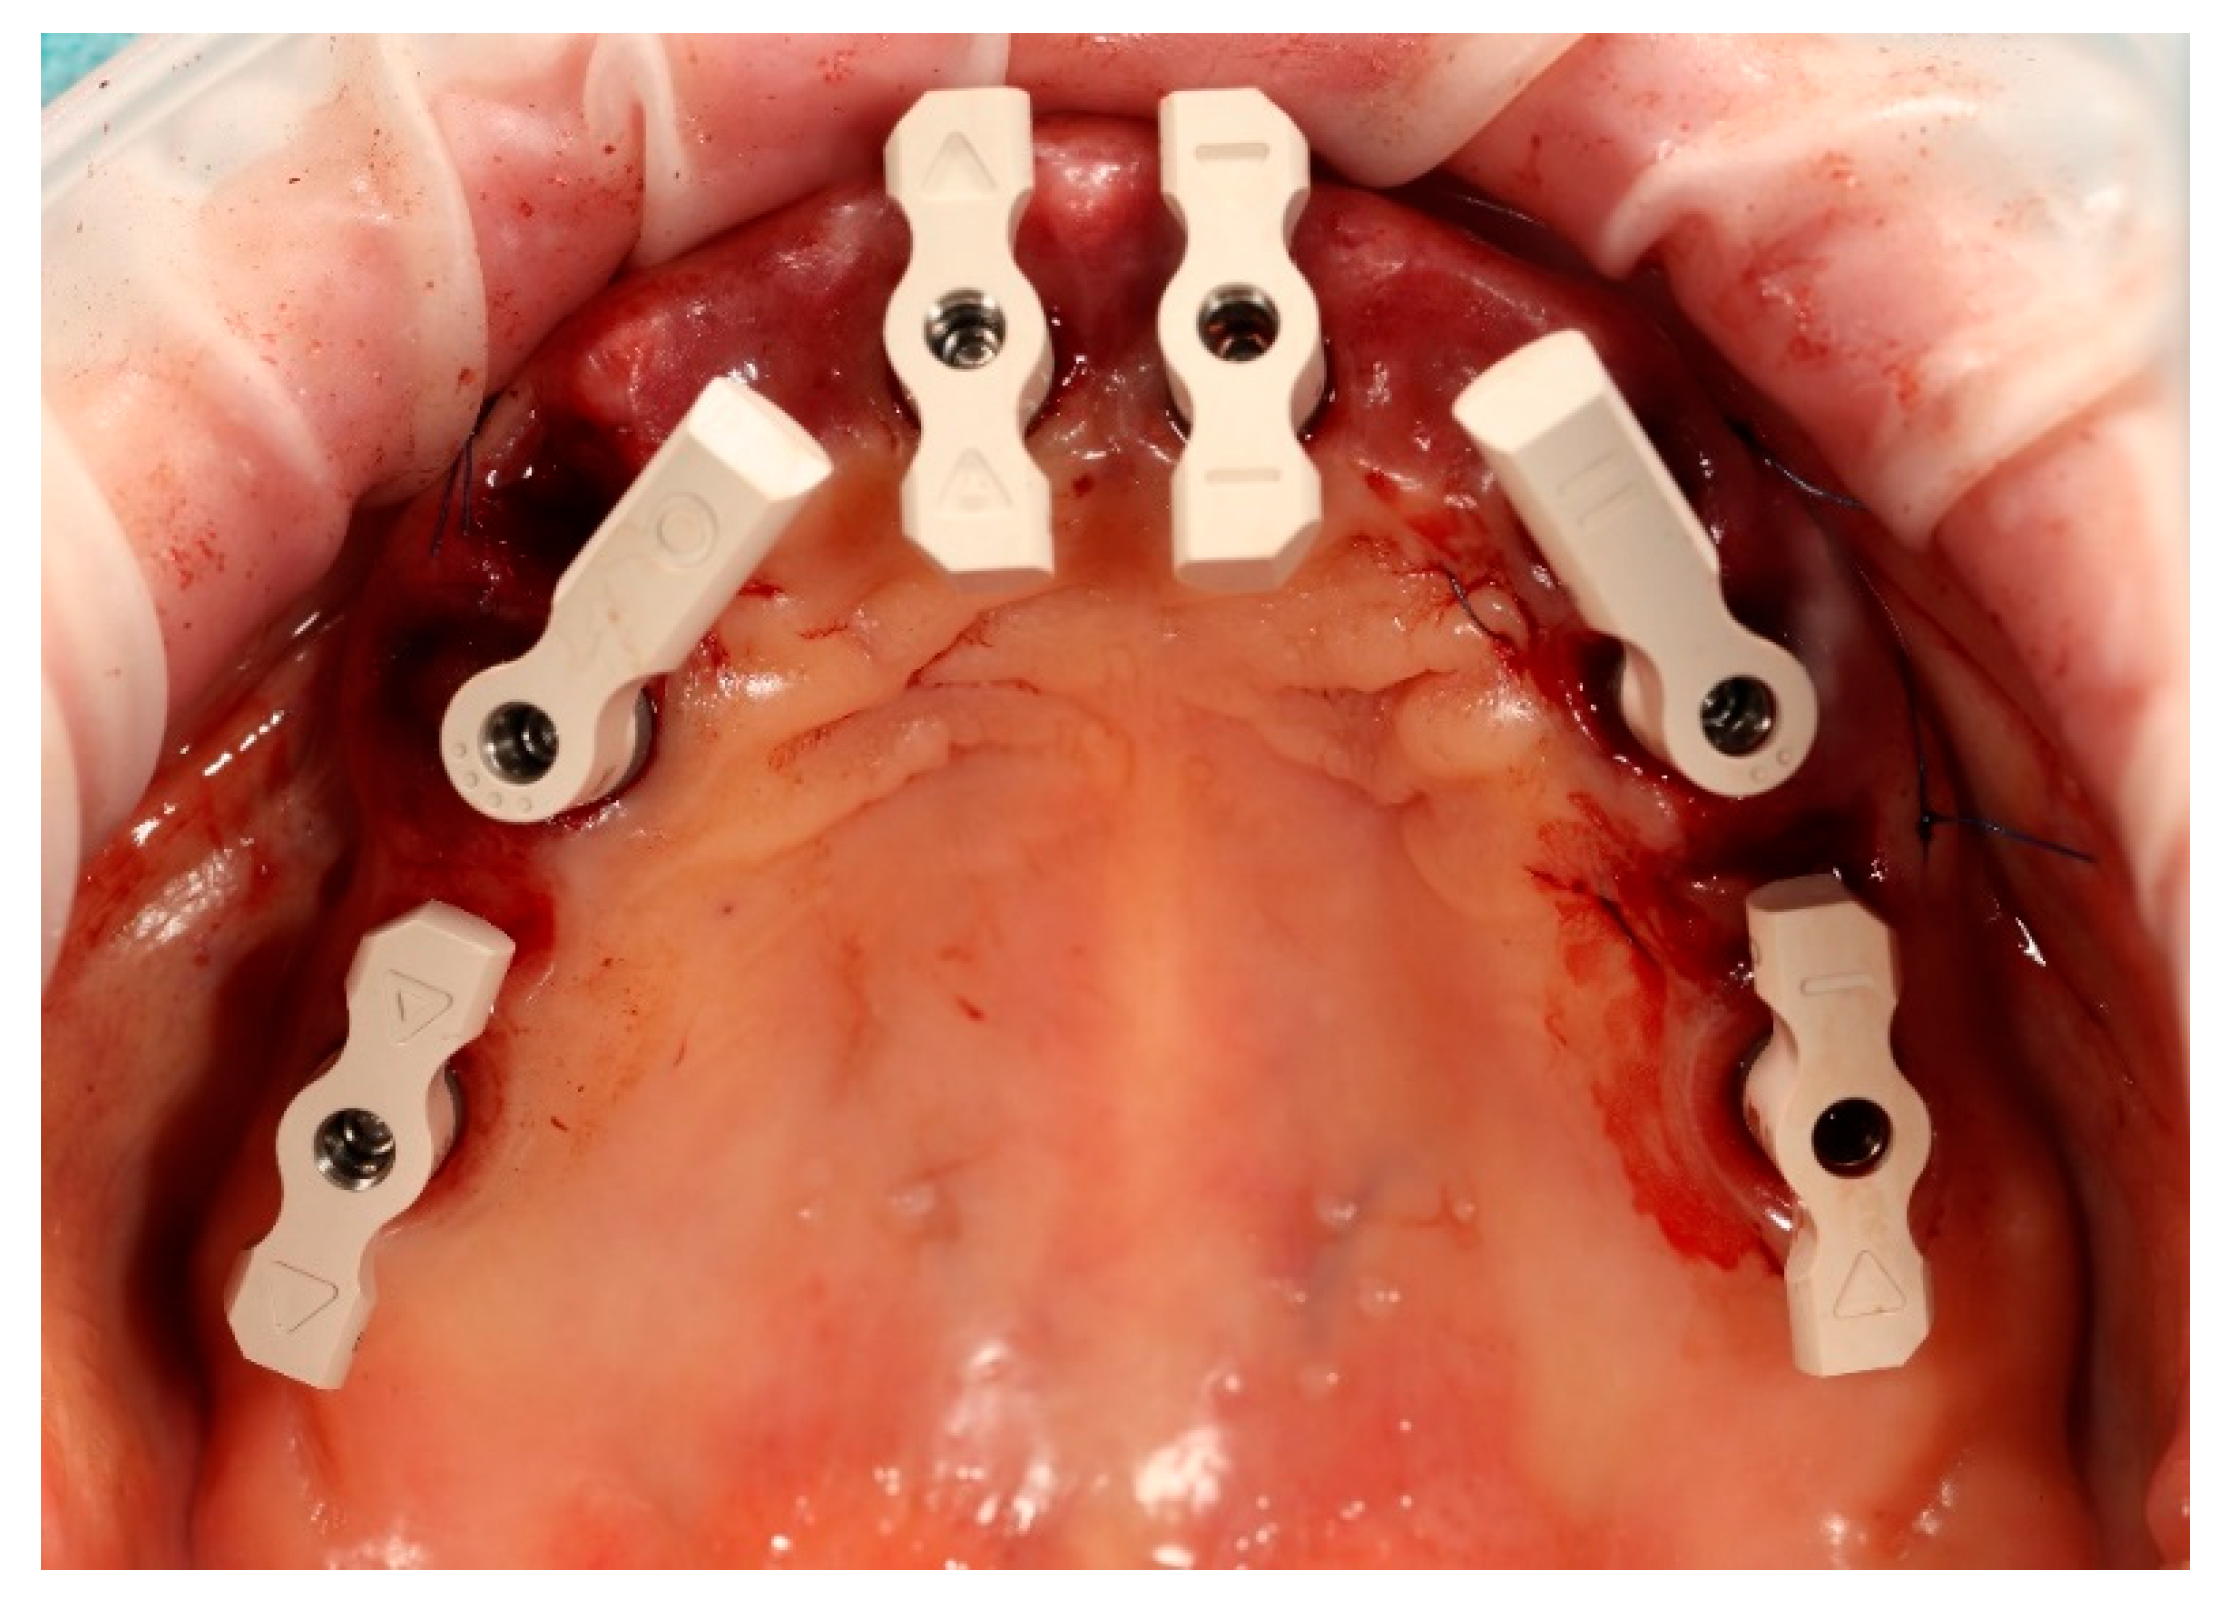

Simultaneously, the existing implant-supported crowns in positions 16 and 26, as well as the anterior implant-supported bridge, were unscrewed from the supporting implants. Multi-unit abutments were then selected and secured onto all six supporting implants, including the newly placed implants at sites 14 and 24 (Figure 4).

Figure 4. Multi-unit abutments secured onto all six supporting implants, including the newly placed implants at positions 14 and 24, following removal of the existing restorations.